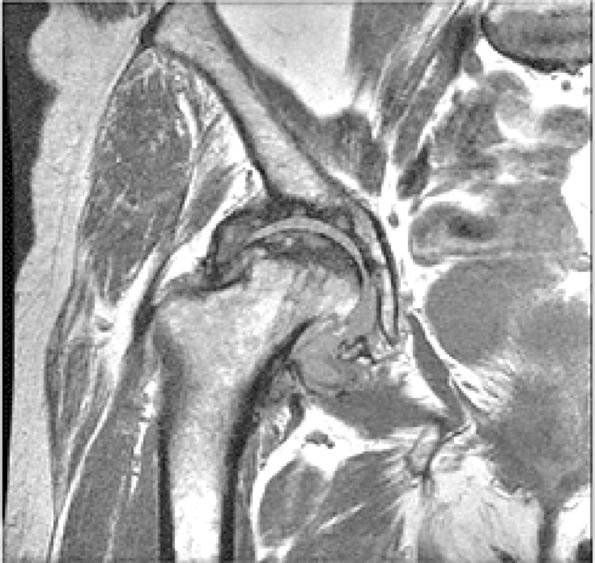

FIGURE 3.48 ● (A) Articular surfaces of the hip joint comprise the acetabulum of the hip bone and the head of the femur. (B) A sagittal MR arthrogram of the hip demonstrating capsular distention and the articular relationship of the femoral head (H) to the anterior (A) and posterior (P) aspects of the acetabulum and ilium (I). Fat-suppressed T2-weighted fast spin-echo.